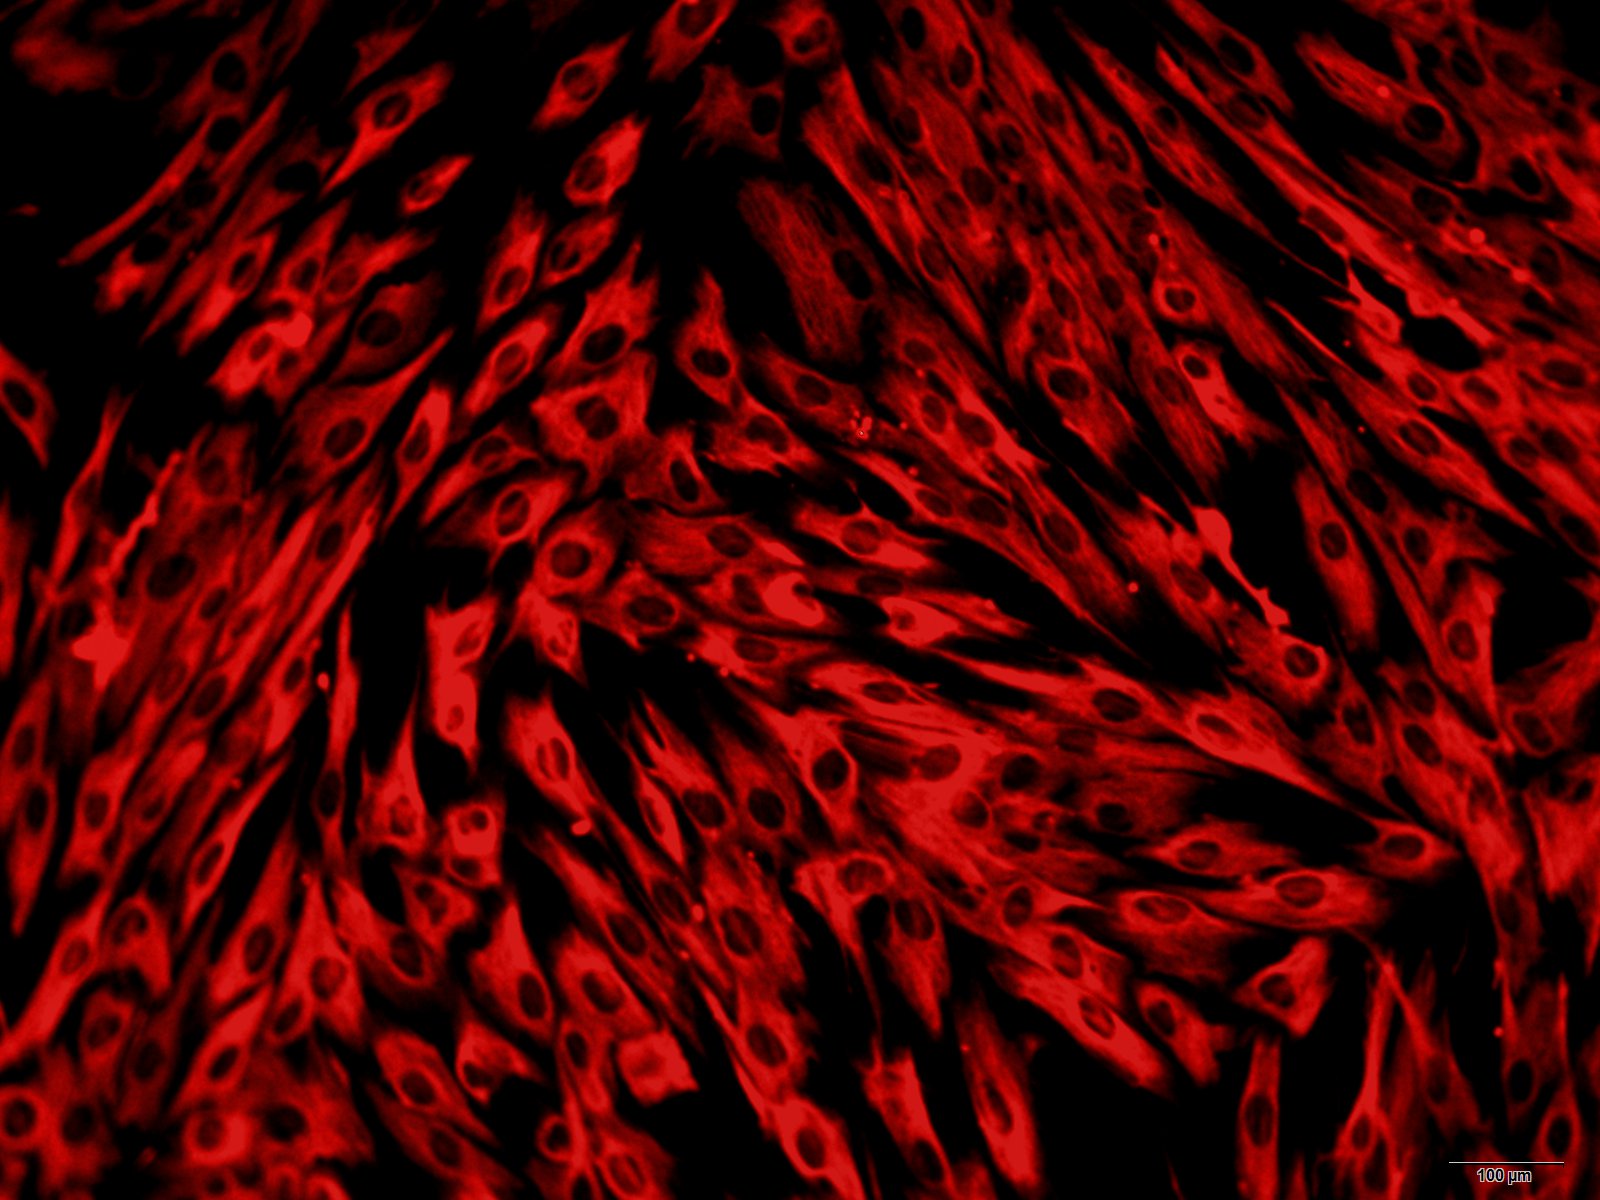

本公司生产的大鼠心肌成纤维细胞采用酶解法制备而来,细胞总量约为5×105/T25方瓶,波形蛋白(Vimentin)、盘状结构域受体(DDR2)免疫荧光染色呈阳性,细胞纯度可达90%以上,且不含有HIV-1、 HBV、HCV、支原体、细菌、酵母和真菌等。